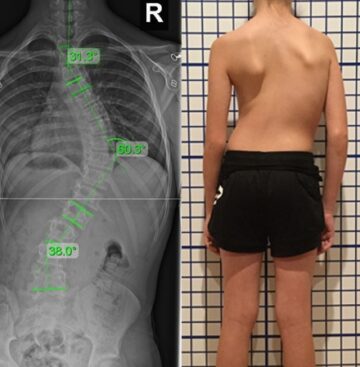

اعوجاج العمود الفقري عند البنات: الأسباب والأعراض والعلاج المبكر للأهل يُعد اعوجاج العمود الفقري عند البنات من أكثر المشكلات الصحية التي تشغل بال الأهل، خصوصًا في مرحلة المراهقة. كثير من الأمهات والآباء يلاحظون ميلان

اعوجاج العمود الفقري عند الأطفال | الأسباب، الأعراض، وطرق العلاج المبكر يُعد اعوجاج العمود الفقري (الجنف) من أكثر مشكلات العمود الفقري شيوعًا عند الأطفال والمراهقين. تشير الدراسات إلى أنه يصيب ما يقارب 3% من

متى تزيد سرعة تدهور اعوجاج العمود الفقري (الجنف) عند الأطفال والمراهقين يُعد اعوجاج العمود الفقري (الجنف) من الحالات التي تتطور تدريجيًا مع مرور الوقت، لكن سرعة التدهور تختلف من مريض لآخر. ففي مرحلة الطفولة